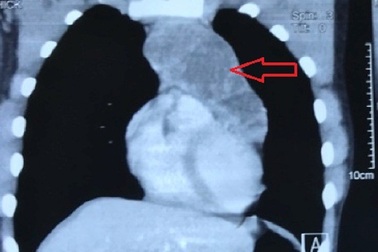

Khối u nặng 4kg ngay giữa lồng ngực bệnh nhânNgày 2/11, Bệnh viện Bạch Mai cho biết thực hiện thành công ca phẫu thuật cắt khối u trung thất có kích thước khổng lồ cho nữ bệnh nhân 41 tuổi.

Ngực nhói đau, chàng trai trẻ không ngờ mang khối u to khủng trong ngựcKhối u trung thất có kích thước lớn, đường kính lên đến 15cm, nặng 1kg. Trước đó từ nhỏ thi thoảng bệnh nhân thấy nhói đau ở ngực nhưng chỉ thoáng qua.

Mọc thêm khối u to như quả cam trong lồng ngực, nam thanh niên suýt tử vongNhập viện trong tình trạng đau nhói ngực khi ho, nam thanh niên được bác sĩ xác định có khối u lớn to như quả cam nằm ngay vùng trung thất đe dọa tính mạng.